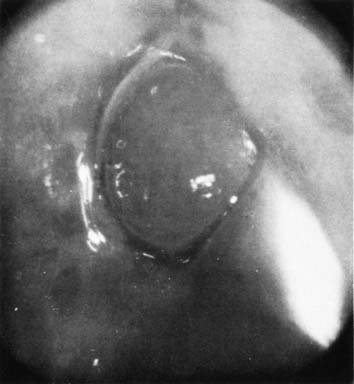

A common benign finding, nabothian cysts are present on the portio of the cervix and are thought to arise in areas of active metaplasia. They represent occlusion of the mucous-secreting glands of the cervix underneath a squamous covering with mucin collecting in a cystic area (Fig. 2). Usually these are small (less than .5 cm) and can be multiple; however, cysts up to 5 cm or greater in diameter have been described. They should have a smooth glistening surface with clear or slightly milky contents (Fig. 3). Deviations from this smooth surface, such as erosions or vascular anomalies, should be further investigated with colposcopy and biopsy. Clearly, very large cysts have secondary symptoms (such as pressure, heaviness, or urinary retention) unlike the absence of symptoms that characterizes the majority of nabothian cysts.

Fig. 2. Multiple small nabothian cysts of the cervix.

Fig. 3. Nabothian cysts of the cervix (×3).